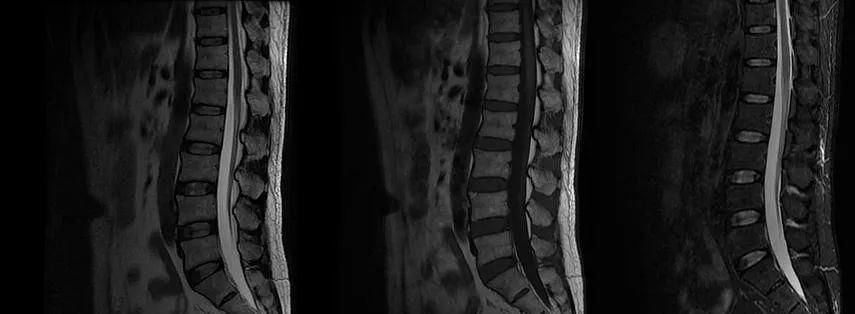

定位:周围神经?糖尿病周围神经病也可累及下肢周围神经,出现类似脊髓病的表现,但患者无糖尿病史,且神经电图不支持。那么吉兰-巴雷综合征呢?患者发病前无前驱感染史,查体无颅神经受损,四肢肌力 V 级,且存在明确的感觉平面,余未见明显异常,神经电生理检查未见明显异常,故不考虑,所以接下来,我们定位在脊髓,进一步完善胸腰段 MRI,如下图:

遗憾的是胸腰部 MRI 中 T1、T2、STIR 均未见明显异常,我们进一步完善头部 MRI,如下图: